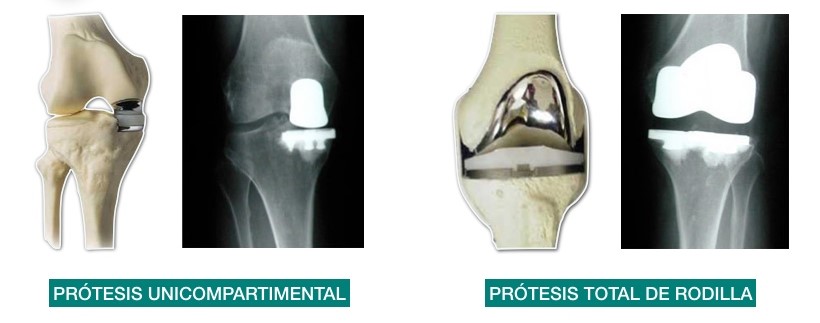

Existen diversos tratamientos quirúrgicos (lavado articular artroscópico, osteotomías, cirugía del cartílago), pero la implantación de una prótesis total de rodilla (PTR) sigue siendo el método de referencia definitivo en el tratamiento de la enfermedad. La PTR ha mejorado significativamente la calidad de vida de los pacientes con gonartrosis avanzada4. De hecho, en nuestro país, la implantación de una PTR suele reservarse para pacientes con grados radiológicos graves (3 y 4 KL), sin mejoría tras tratamiento médico previo y preferentemente mayores de 60-65 años. Sin embargo, en la práctica diaria del traumatólogo la realidad es que sigue siendo dificultoso decidir si un paciente de 45 años de edad, con dolor y grado 3 KL, es merecedor de una PTR, o si un paciente de 75 años, con dolor y un grado 2 KL, no lo es. Esta dificultad viene dada también por la posibilidad de complicaciones quirúrgicas y la discordancia entre las expectativas del paciente y el cirujano tras implantar una PTR5. En todo caso, la variabilidad al indicar una PTR sigue siendo muy amplia. El tratamiento no quirúrgico de la gonartrosis se divide en farmacológico y no farmacológico. Quizá este último sea uno de los objetivos de estudio futuro, ya que el impacto de campañas de educación sobre la enfermedad, control de peso y mejora de la capacidad osteomuscular mediante ejercicio adecuado se implanten en los sistemas sanitarios evolucionados.